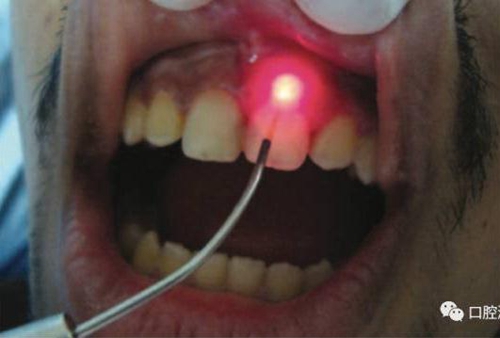

對(duì)瘺管位置進(jìn)行激光氣化

氣化消融發(fā)炎組織:利用高強(qiáng)度激光對(duì)根尖區(qū)域的腫脹、肉芽組織加熱使之氣化。如果發(fā)現(xiàn)有瘺管存在,可以將激光光纖插入瘺管中,采用間歇式發(fā)射激光的方式,邊發(fā)射激光,邊抽出光纖。此時(shí)務(wù)必注意激光功率不宜過(guò)高,而且光纖抽出速度不宜太慢或太快,以出現(xiàn)水汽為宜。